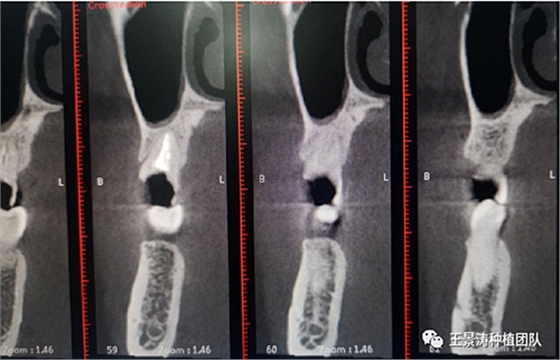

其次初期穩(wěn)定性的獲得,前牙美學(xué)區(qū)種植體的初期穩(wěn)定性主要是依靠腭舌側(cè)骨板及基底骨來獲得的。后牙區(qū)的穩(wěn)定性主要依靠多根牙的牙槽間隔及根尖到重要解剖位置的高度的骨質(zhì)獲得(主要是竇嵴距和管嵴矩的高度,還要參考植入種植體的長度),因此術(shù)前仔細(xì)測量牙槽間隔與根尖至重要解剖結(jié)構(gòu)的高度是后牙即刻種植的關(guān)鍵因素之一。

左側(cè)下頜第二磨牙及右側(cè)下頜第一磨牙同時(shí)即刻種植病例?;颊吣贻p女性,無系統(tǒng)性疾病。37及46殘冠及殘根,且46劈裂,無法冠修復(fù),必須拔除。37根尖慢性炎癥,大量肉芽組織存在,46根分叉較高,根分叉骨質(zhì)尚可。CBCT示:根尖骨質(zhì)至下牙槽神經(jīng)管距離可滿足種植體的初期穩(wěn)定性,遂考慮即刻種植,并在種植體周邊填入骨粉并覆蓋骨膜,雙側(cè)的種植體初期穩(wěn)定性相差無幾,但考慮到37根尖慢性炎癥較大,遂給予埋入式種植。